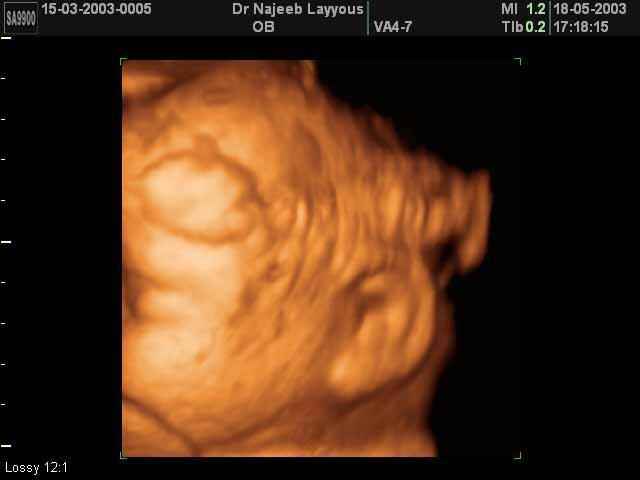

- Les Photos d'Ultrasons du visage du fétus

- 3D Photos échographie du profile du fœtus

- es Photos d'Ultrasons du visage du fétus